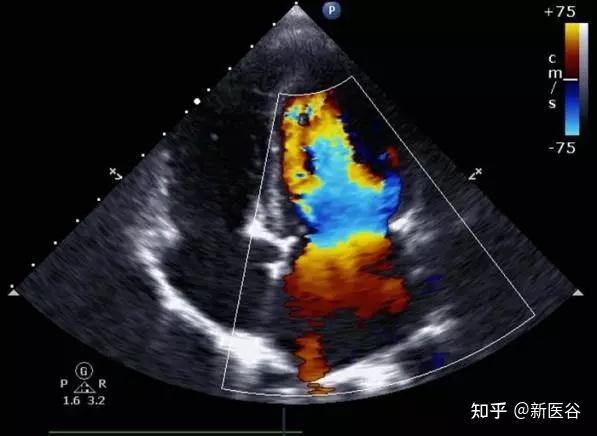

彩色血流成像就是基于血流的多普勒效应来成像的。(多普勒效应:当声源或接收体或两者同时相对介质运动时,接收体接收到的声波频率发生变化的现象。)

在上述机制图中,后续的编码和显像就是将储存的血流数据转换为色度信号,即上色。但上色可不是随心所欲的哦!

关于颜色的选择可是有严格的规定的,现在通用的是国际照明委员会规定的三原色:红、绿、蓝。

其他颜色都是由这三种颜色混合而成,如流向探头的血流出现湍流,将出现红色加绿色形成的黄色,流离探头的血流出现湍流,将出现蓝色加绿色形成的青色。